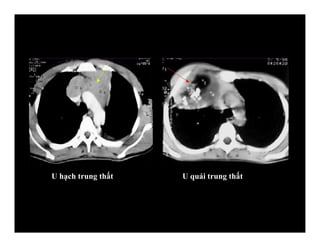

U hạch trung thất U quái trung thất